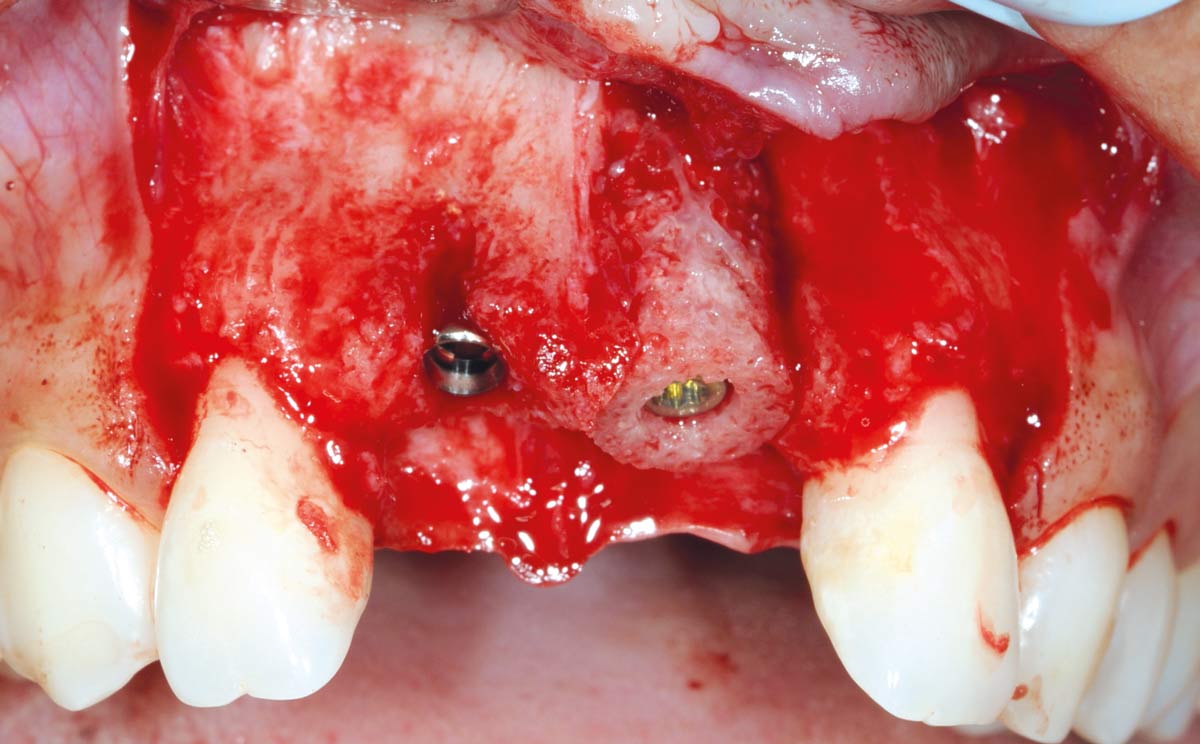

10/26 - Fixation of maxgraft® bonering with a Straumann® SLActive Bone Level Tapered ImplantBone augmentation in aesthetic zone with maxgraft® bonering - Dr. A. Patel

11/26 - Implantation in region 11Bone augmentation in aesthetic zone with maxgraft® bonering - Dr. A. Patel